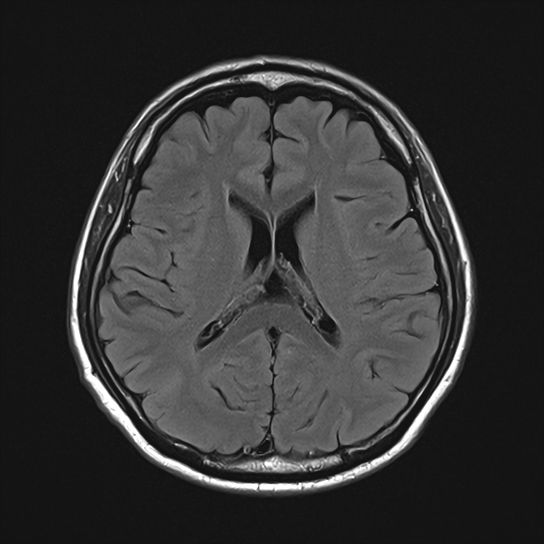

脳にできる良性・悪性の腫瘍も、MRIによって早期に発見できる可能性があります。 - 脳萎縮の程度:

加齢による脳の萎縮の程度を評価し、認知症のリスクなどを判断する手助けとなります。 - その他の脳疾患の早期発見:

多発性硬化症や奇形など、様々な脳の異常を発見する可能性があります。